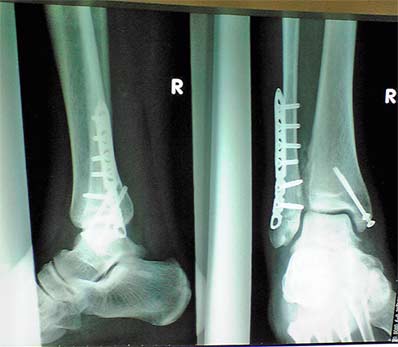

2007050201.jpg

これが現在の状況です。

リハビリも順調なので今まで通りのリハビリを自宅で行って良いと言うことです。

ほんまにええのか?二足歩行もしょっちゅうしてるで?

では、今まで通りゆっくりと順調に自主リハビリ頑張ります(笑)